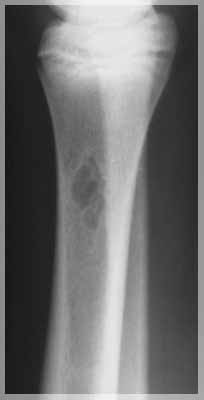

Во второй группе было 11 детей с диагнозами: костная киста трубчатой кости, патологический перелом кости, остеомиелит с разрушением головки бедренной кости. Возраст больных детей составлял от 11 месяцев до 16 лет. Рентгенологически отчетливо прослеживались патологические изменения и дефекты костных тканей. Общепринятые методики требовали хирургического вмешательства. В трех случаях требовалось протезирование с заменой костной ткани, что влекло за собой инвалидность и нарушение общего развития опорно-двигательного аппарата ребенка. В двух других случаях ранее было проведено оперативное лечение кисты. После операции наблюдался рецидив и дальнейшее прогрессирование заболевания.

Во второй группе в апреле 2004 г. длительность лечения составила от 6 до 10 месяцев. Во всех случаях наблюдалась положительная динамика. Для 9 пациентов из 11 по характеру восстановления костных тканей можно прогнозировать дальнейшее улучшение до полного излечения. Двое детей, у которых наблюдался рецидив после оперативного лечения, в настоящее время полностью здоровы.